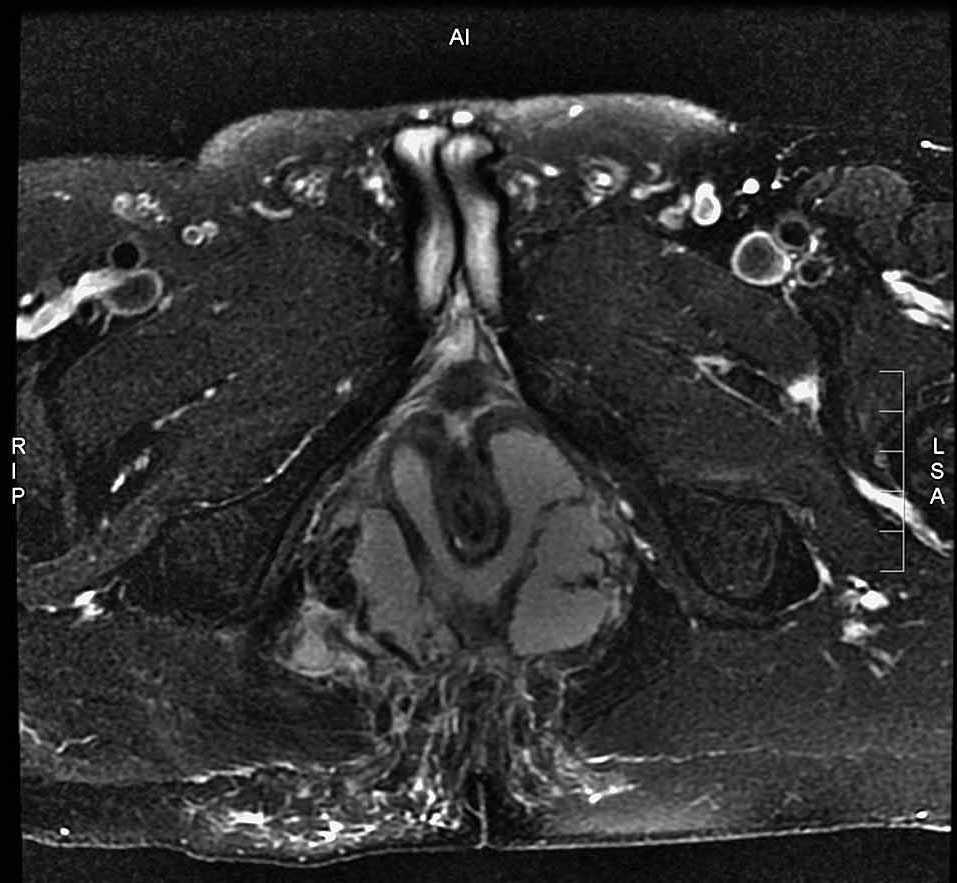

En la exploración física perianal no se apreciaban signos claros de absceso perianal. La resonancia magnética mostró un absceso perianal con componente interesfinteriano y transesfinteriano en herradura que ocupaba prácticamente la totalidad de ambos espacios isquiorrectales y con extensión craneal hasta el músculo elevador del ano sin sobrepasarlo (figs. 1 y 2).

Fig.1.

Fig.2.